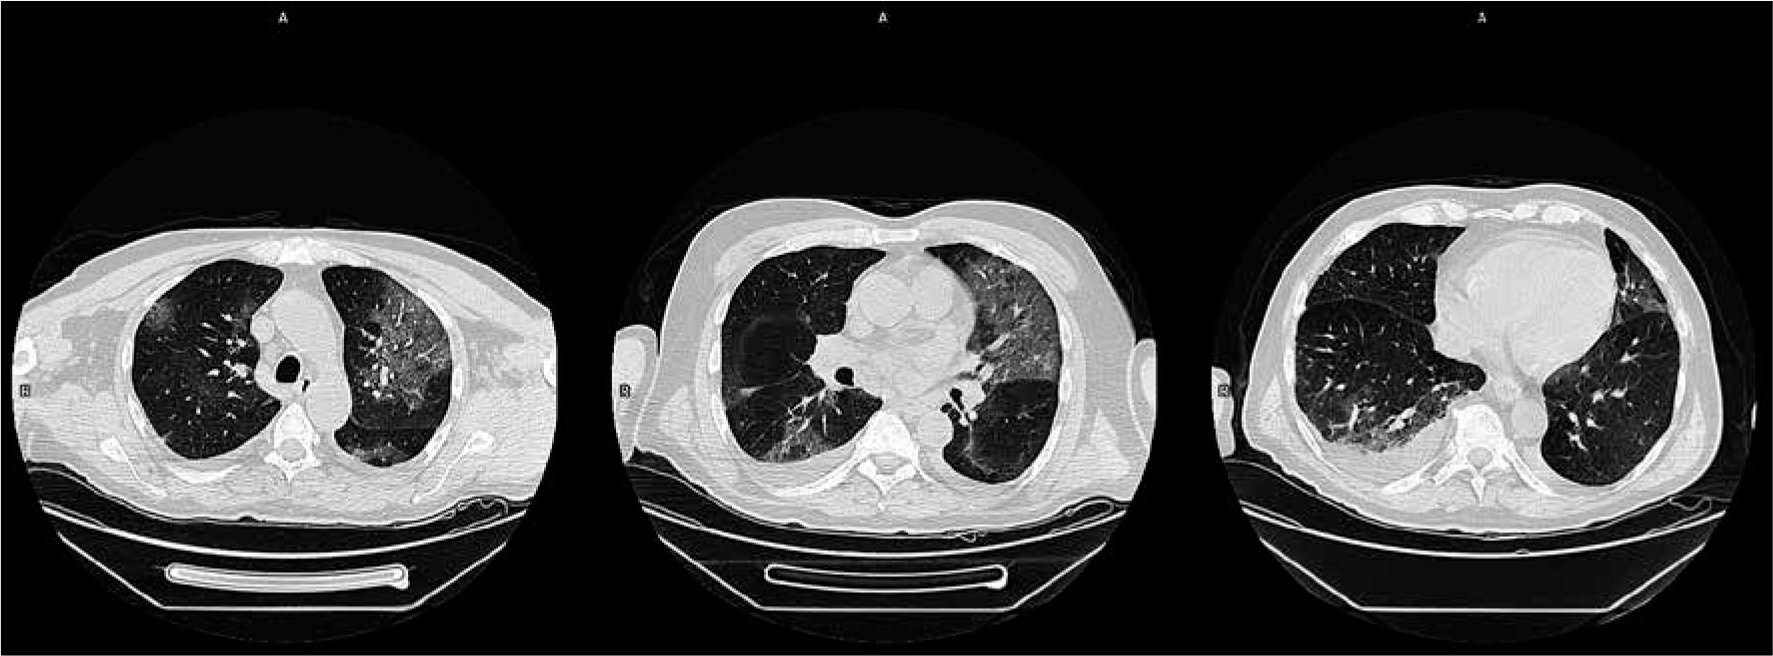

Figure 6

Computed tomography scans of a COVID-19-positive patient in axial projection. Lungs were assessed in modified total severity scoring system (mTSS) at 6 points. The main features of lung involvement are regions of ground glass opacity; therefore, the overall mTSS score is 6A

Computed tomography scans of a COVID-19-positive patient in axial projection. Lungs were assessed in modified total severity scoring system (mTSS) at 18 points. The main features of lung involvement are consolidations; therefore, the overall mTSS score is 18C